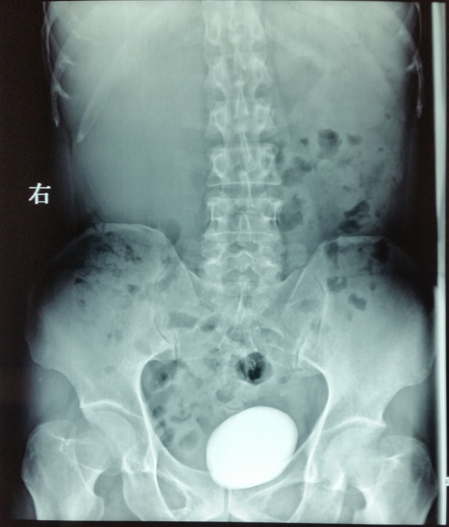

腹部平片示膀胱巨大结石

日前,泌尿外科王金根主任医师为一位罕见的肾、输尿管、膀胱多发性肿瘤患者成功实施了切除手术,一次性完整切除右肾、右输尿管和全膀胱,术后没有并发症,病理切片证实为腺癌,各切缘均未见癌细胞(表明切除彻底),患者顺利康复出院。患者是一位54岁男性,因反复肉眼血尿2年余,右侧腰痛2月余入院。入院后经相关检查很快确诊了病情:右侧肾盂肾盏、右输尿管全长和膀胱内均生长了大量肿瘤,同时合并感染发烧,膀胱内还有一个巨大结石,此外还存在严重贫血和营养不良,全身水肿。手术切除是患者目前唯一的治疗选择。由于长期梗阻,右侧肾盂肾盏和输尿管重度扩张,加上近期合并感染,肾脏周围广泛粘连,手术分离过程中肾脏及输尿管壁极易破损,一旦破损将会导致肿瘤扩散,严重影响疗效。因此手术难度极大,风险很高,对手术医生的技术要求非常高。王金根博士组织全科专家反复讨论制定治疗方案,并亲自带领治疗组进行充分细致的术前准备。2014年6月9日,由王博士主刀,在全麻下为患者施行了手术。手术中发现患者右肾体积巨大,与腰背部肌肉、肝脏、结肠和下腔静脉等重要器官广泛紧密粘连,手术难度比术前估计的还要大。为了解除患者的病痛,挽救患者的生命,王金根博士、贾灵华硕士和包佑根医生等组成的手术小组迎难而上,历经八个小时的艰苦努力,终于将患者的右肾、输尿管和膀胱完整切除,邻近器官完好无损。